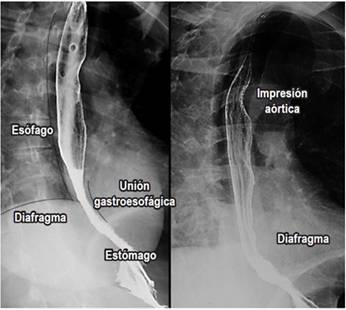

Se debe evaluar la columna del medio de contraste, el vaciamiento esofágico y la integridad de las estructuras anatómicas (paredes esofágicas y unión esofagogástrica) 1,2,3,4 (Figura 1).

Se evalúan 3 porciones anatómicas diferentes según su localización 1,2,3,4:

Esófago cervical: desde la faringe hasta la sexta vértebra cervical y el borde inferior del cartílago cricoides.

Esófago torácico: desde la sexta vértebra cervical hasta el hiato esofágico.

Esófago abdominal: desde el hiato esofágico hasta la unión esofagogástrica (Figura 1).